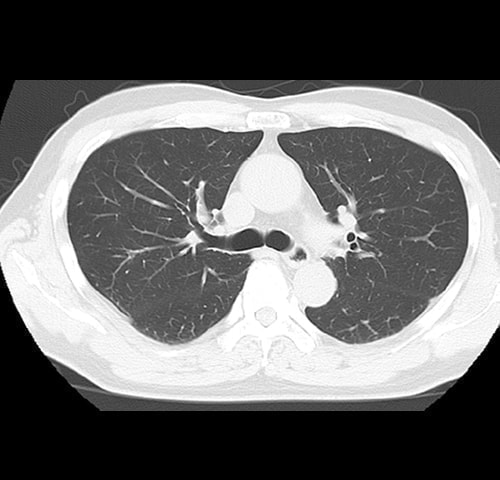

(肺炎・肺気腫・ 肺がん)病変

※胸部レントゲン写真で解りにくい 肺がんの発見

肺